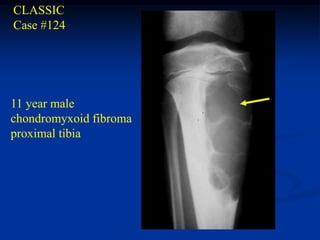

CLASSIC

Case #124

11 year male

chondromyxoid fibroma

proximal tibia